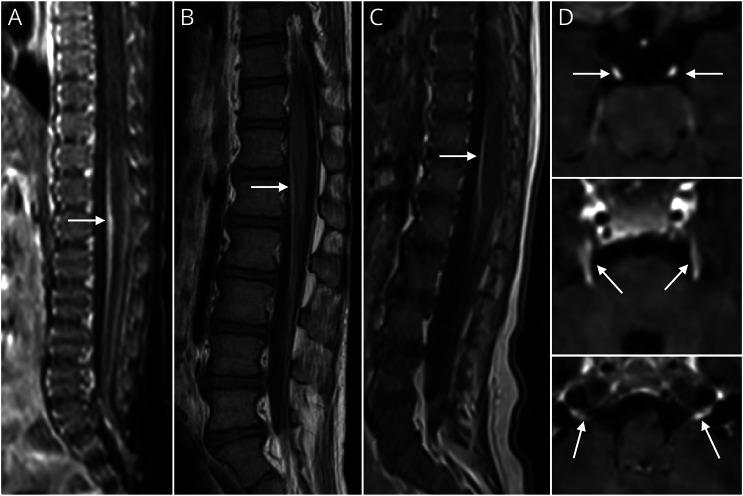

Three patterns of clinical course and survival were observed, distinguished by main category of symptoms: neurologic, hepatic, and gastrointestinal. A total of 24 patients needed urgent neurointensive care for tonic-clonic seizures, myoclonic epilepsy, and status epilepticus, occasionally precipitated by valproate administration. Other neurologic symptoms included dystonia, cerebellar ataxia, and peripheral neuropathy. We report 6 POLG-deficient patients with polyradiculoneuropathy mimicking subacute Guillain-Barré syndrome and provide postgadolinium MRI evidence of diffuse cranial nerve root and enhancement, suggesting these disorders have an inflammatory component. Children presenting with enteral nervous system involvement had vomiting, gastroparesis, and chronic intestinal pseudo-obstruction. They had later ages of onset and lived much longer. Primarily, hepatic presentations had the earliest onset and shortest survivals. Secondary hepatic failure was frequently precipitated by valproate administration given before diagnosis to patients with focal impaired awareness seizures or absence of seizures. These POLG deficiencies were often fatal, with age at death ranging from 3 months to 10 years, with a significant difference in survival between the 3 clinical forms; 6 of the 40 children did survive. No genotype-phenotype correlations were found for the 3 clinical course types.

观察到三种临床病程和生存模式,以主要症状类别区分:神经、肝脏和胃肠道。共有24例患者因强直阵挛性发作、肌阵挛性癫痫和癫痫持续状态需要紧急神经重症监护,这些情况偶尔由丙戊酸盐给药诱发。其他神经症状包括肌张力障碍、小脑共济失调和周围神经病变。我们报告了6例POLG缺乏患者,其多神经根神经病类似亚急性吉兰-巴雷综合征,并提供了钆增强磁共振成像证据,显示弥漫性颅神经根强化,提示这些疾病有炎症成分。出现肠神经系统受累的儿童有呕吐、胃轻瘫和慢性肠假性梗阻。他们起病年龄较晚,存活时间更长。主要表现为肝脏症状的患者起病最早,存活时间最短。在诊断前给予有局灶性意识障碍发作或无发作的患者丙戊酸盐治疗,常导致继发性肝衰竭。这些POLG缺乏症通常是致命的,死亡年龄在3个月至10岁之间,三种临床类型的生存情况有显著差异;40例儿童中有6例存活。在三种临床病程类型中未发现基因型与表型的相关性。

Enhancement of cranial nerves, conus medullaris, and nerve roots in POLG mitochondrial disease.POLG线粒体疾病中脑神经、脊髓圆锥和神经根的强化表现

Neurol Genet. 2019 Sep 6;5(5):e360. doi: 10.1212/NXG.0000000000000360. eCollection 2019 Oct.

Cranial nerve and cervical root enhancement in an infant with polymerase gamma mutation mitochondrial disease.患有聚合酶γ基因突变线粒体疾病的婴儿的颅神经和颈神经根强化。

Pediatr Neurol. 2014 Nov;51(5):734-6. doi: 10.1016/j.pediatrneurol.2014.06.015. Epub 2014 Jun 26.